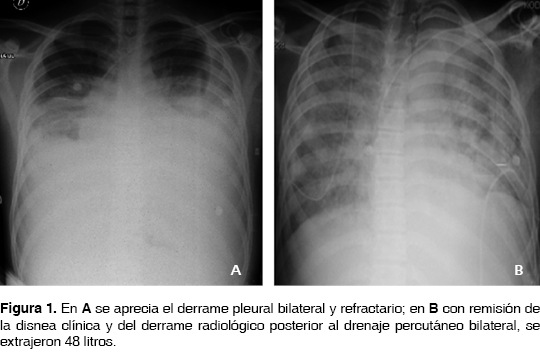

Los paraclínicos mostraron anemia con hemoglobina de 7.7, leucocitos de 6,200 con neutrófilos de 72%, monocitos de 8.7% y plaquetas de 251 mil; velocidad de sedimentación globular de 52 mm/h, serología para VIH y baciloscopias negativas, proteinuria y hematuria. El líquido pleural expuso un exudado con proteínas de 4,000, glucosa de 99 mg/dL y celularidad escasa con cultivos negativos, la adenosina desaminasa en 32 U/L, la biopsia del conglomerado ganglionar axilar mostró hiperplasia linfoide y los anticuerpos antiDNA y ANAS positivos. De la expectoración inducida se reportó prueba de PCR para M. tuberculosis de 0.715 (positivo), iniciando tratamiento antifímico. Evolucionó con síndrome nefrítico, se reunieron los criterios diagnósticos para lupus eritematoso sistémico (anemia hemolítica, derrame pleural, glomerulonefritis y anticuerpos positivos). Se agregó bloqueo incompleto de rama derecha en el electrocardiograma y la ecocardiografía mostró pequeño derrame pericárdico con presión de la arteria pulmonar de 30 mmHg y fracción de eyección sistólica del 59%. La frotis de sangre periférica fue normal. Se incrementó la disnea y dificultad respiratoria a pesar del tratamiento antifímico e inmunosupresor, radiológicamente fue corroborado derrame pleural bilateral, cursando con bradicardia sintomática que requirió de la colocación de marcapasos e inicio de anticoagulación por trombosis de la vena ilíaca izquierda. Después de dos toracocentesis evacuadoras que remitían temporalmente disnea, se decidió insertar un catéter percutáneo vía intercostal en cada hemitórax y obtener durante 28 días un total de 48 L de líquido pleural, se evitó la inserción de una sonda pleural por el riesgo probable de pleuresía tuberculosa y la posibilidad de una fístula pleurocutánea agregada (figura 1).

La actividad lúpica fue tratada prontamente con metilprednisolona en altas dosis, gama globulina intravenosa y rituximab sin mejoría alguna; fueron corregidos estados trasudativos de hipoalbuminemia, sobrecarga hídrica e hiponatremia. Bajo este panorama es considerado derrame pleural masivo, bilateral y refractario a manejo conservador, se realiza tratamiento quirúrgico con drenaje pleural y adherensiolisis del pulmón izquierdo atrapado con toma de biopsia pleural y pleurectomía parcial con pleurodesis química con yodo povidona al 1% por toracoscopia videoasistida. Del hemitórax derecho, una vez descartado por toracoscopia la presencia de un pulmón atrapado y confirmando la expansión pulmonar, se decidió instilar bajo visión pleurodesis química con yodo povidona al 1% y pinzamiento por cuatro horas de la sonda pleural (figuras 2 y 3). Se instiló vía intrapleural por tubo de toracostomía derecha y una sesión más con yodo povidona sin complicaciones. Con evolución satisfactoria fueron retirados los drenajes pleurales al tercer y cuarto día y documentadas la expansión pulmonar clínica y radiológica; y sin recurrencias a dos años de vigilancia y tratamiento médico inmunosupresor. El reporte histopatológico documentó pleuritis aguda y crónica inespecífica mayormente acentuado alrededor de los vasos sanguíneos, con hiperplasia mesotelial e infiltrado linfoplasmocitario. La citología del líquido pleural mostró células mesoteliales reactivas mezcladas con linfocitos.